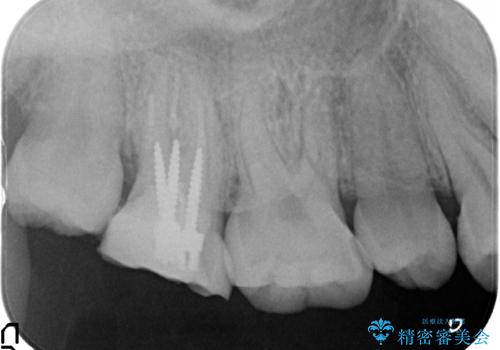

- 他院にて右上7番目の歯の根管治療を行ったが鈍い痛みが治まらないので診て欲しいといらっしゃった方の症例です。

再根管治療を行い症状の消失を確認後、オールセラミッククラウンによる補綴を行いました。